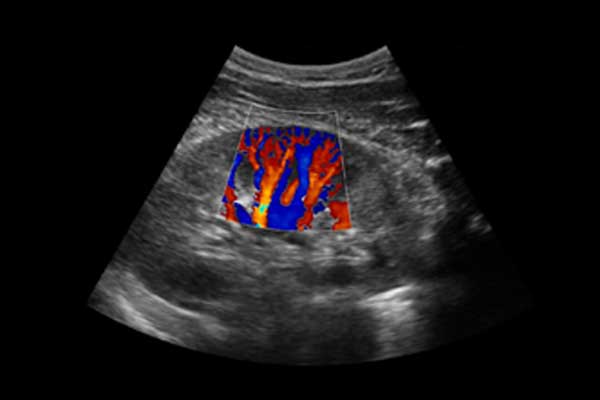

X3便携式彩色多普勒超声诊断系统是一款将小巧机身与卓越性能结合的便携产品。高度集成化的硬件模块,配合时尚前沿的人机工学设计打造了X3,如笔记本电脑般轻薄灵巧的机身、同时也赋予它突破体量限制的优异整机性能。轻便小巧,简单易用。图像清晰,X3可以随时随地满足您的使用需求。

X3搭载了丰富的探头群,可全面满足腹部、泌尿系统、浅表器官、妇科、产科、心脏及外周血管等常规领域应用。轻薄灵巧的主机机身、人性化的台车设计、实用的三探头扩展器、使得它无论在超声科还是在移动诊疗应用中都可以轻松应对。